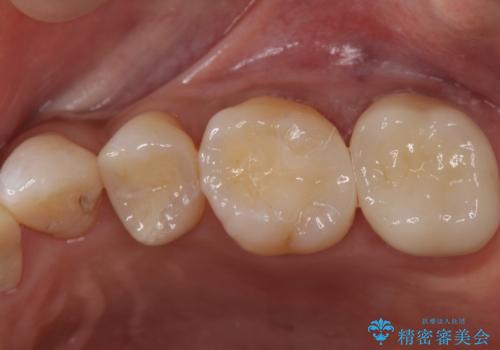

初めは一番奥の歯の樹脂の詰め物のやり替えをする予定でしたが、予想よりも歯の厚みが取れなかったため破折リスクを抑えることを目的にクラウンで修復処置を行いました。

その際手前の歯にも虫歯が確認されたため、こちらはインレーでの修復処置を行いました。

- 左上6:セラミックインレー/77,000円 左上7:仮歯+ジルコニアクラウン/11,000+110,000円費用は治療当時の料金となります

今回はしみる症状も抑えられ、偶然見つかった虫歯も取り切ることができ大変喜んでいただけました。